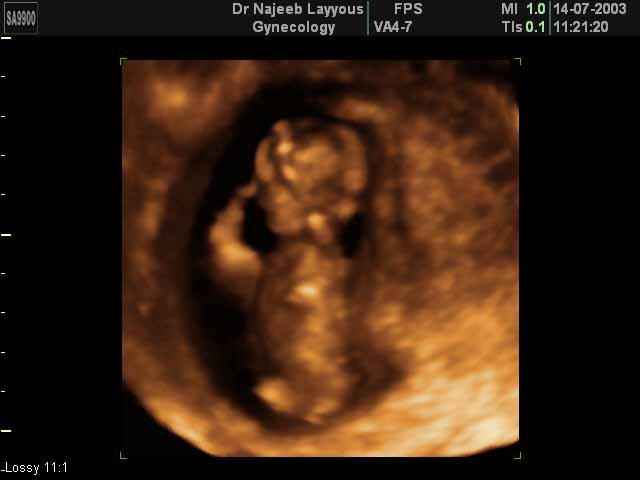

- 3D Photos Ecographie du Premier Trimestre